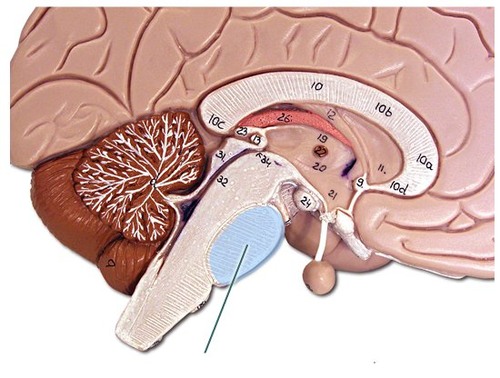

cerebellum (def)

the "little brain" at the

rear of the brainstem; functions

include processing sensory input,

coordinating movement output and

balance, and enabling nonverbal

learning and memory.

rear of the brainstem; functions

include processing sensory input,

coordinating movement output and

balance, and enabling nonverbal

learning and memory.

24

New cards

cerebellum (pic)